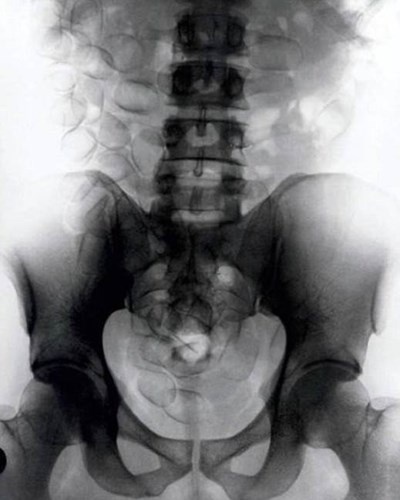

| Vào năm 2002, một người đàn ông 62 tuổi đến từ Pháp đã nuốt 350 đồng xu vào bụng để thay đổi chế độ ăn uống. Ngay sau đó, ông đã lập tức được đưa đến bệnh viện. Các bác sỹ đã phát hiện một khối tiền xu nặng 5,5kg, trông hệt như một quả bóng bowling. |